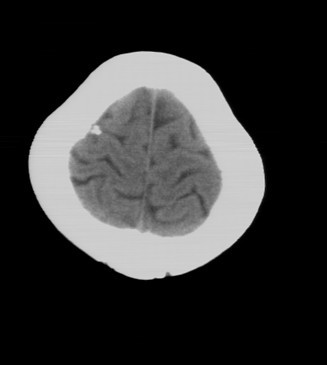

后枕部疼痛来检查的,无任何相关病史

骨瘤吧?

考虑脑膜钙化或小脑膜瘤钙化。

钙化

考虑骨瘤或小脑膜瘤钙化。

脑沟内钙化灶,考虑陈旧性脑膜感染

钙化灶。

钙化灶

考虑脑膜钙化

小脑膜瘤钙化

良性钙斑

考虑脑膜钙化或小脑膜瘤钙化